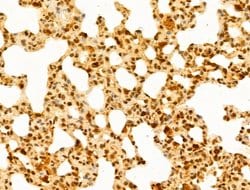

Invitrogen™ GABPB1 Polyclonal Antibody

Antibody detects endogenous levels of total GABPB1.

| Immunohistochemistry (Paraffin), Western Blot, Immunocytochemistry | |

| A synthesized peptide derived from human GABPB1(Accession Q06547), corresponding to amino acid residues V264-D314. | |

| Human, Mouse, Rat | |